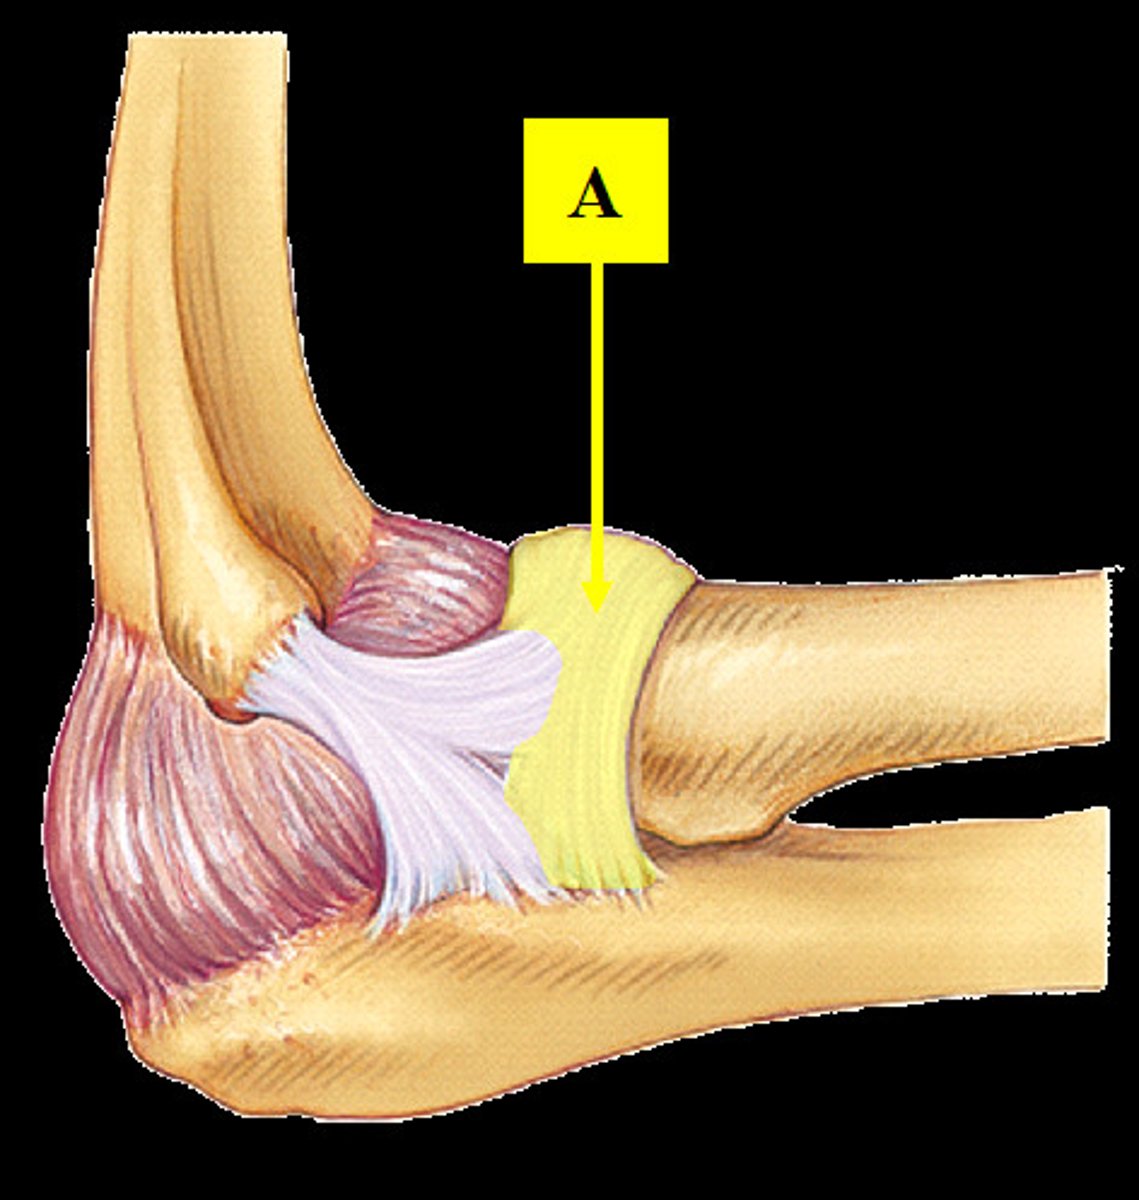

Radial collateral ligament

Anular ligament

Ulnar collateral damage